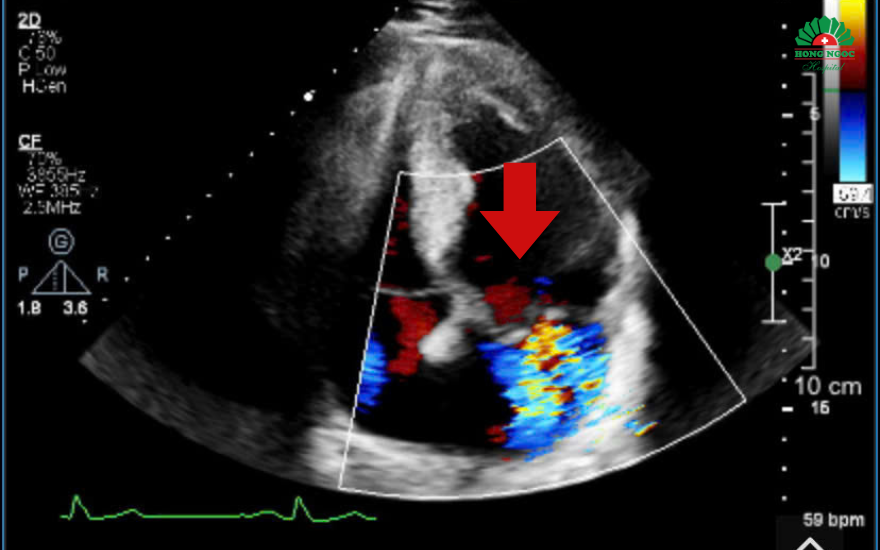

Khi tiến hành siêu âm Doppler tim toàn diện, bác sĩ phát hiện van hai lá bị sa và hở nhiều, khiến máu trào ngược trong tim. Tình trạng này kéo dài đã làm các buồng tim bên trái giãn to, chức năng co bóp của tim bắt đầu suy giảm. Đây là những bất thường khó có thể phát hiện nếu chỉ siêu âm nhanh hoặc đánh giá tổng thể, mà cần khảo sát kỹ từng vùng cơ tim ở nhiều góc độ khác nhau.

Siêu âm tim ghi nhận hình ảnh dòng màu hở van hai lá